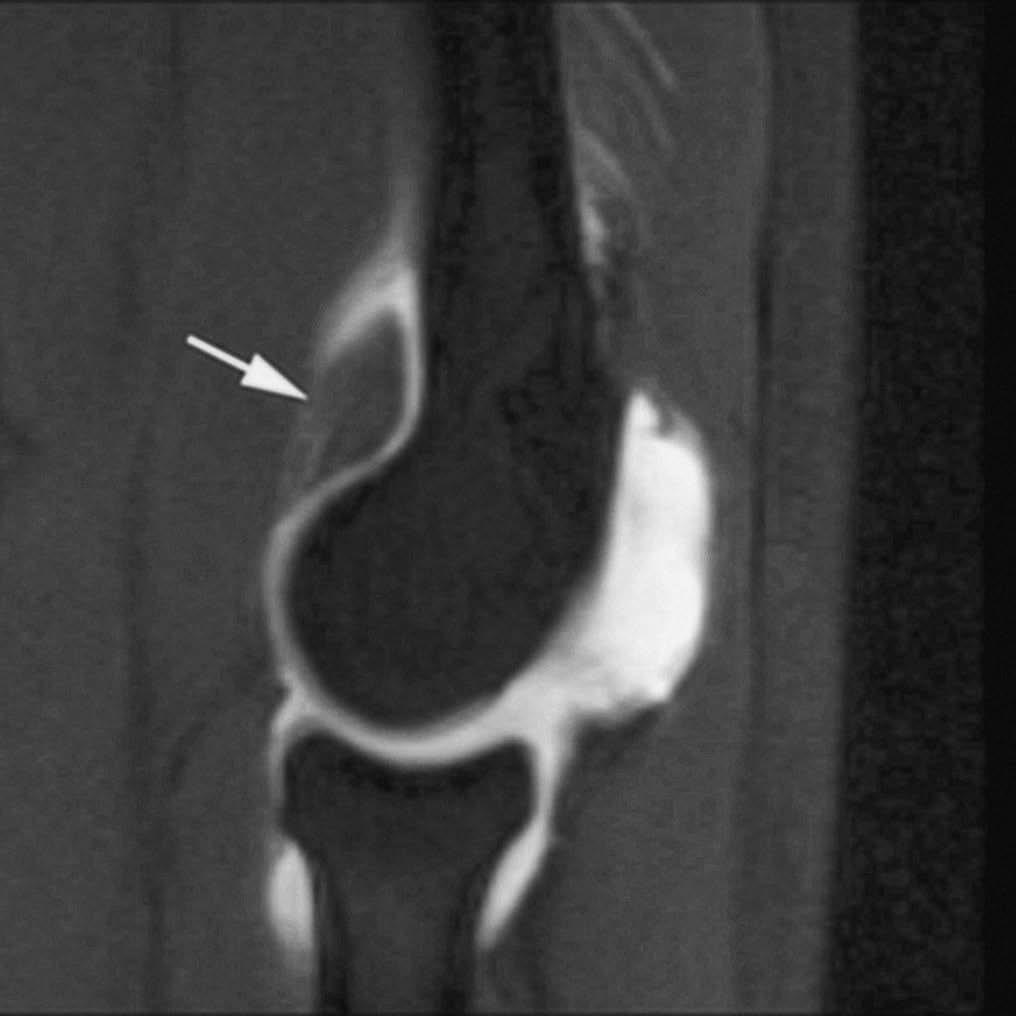

El síndrome del anillo acetabular debería sospecharse a partir de la exploración clínica. La rotura labral actúa como punto de inicio del proceso degenerativo articular. La distribución de las fuerzas a lo largo de la superficie articular se altera y condiciona un impacto repetido de la cabeza femoral en el acetábulo, con desarrollo de defectos condrales y osteoartritis progresiva3,6-10. La RMA permite una valoración precisa de estas lesiones con una excelente correlación con los hallazgos artroscópicos y quirúrgicos. Las roturas displásicas afectan la región superior del labrum, donde es más susceptible al choque repetido con la cabeza femoral (fig. 3). La asociación de las roturas labra les con gangliones quísticos es frecuente en este tipo de pacientes3,8.

Fig. 3.--Displasia de cadera del adulto. Corte axial oblicuo de RMA potenciado en T1 con técnica de supresión grasa. Defecto lineal en el labrum antero-superior (flecha).